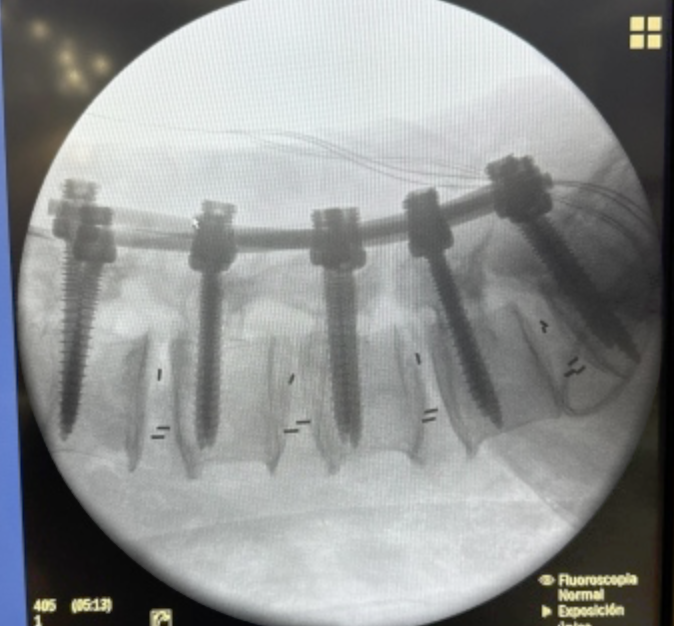

CIRUGIAS

RESULTADOS